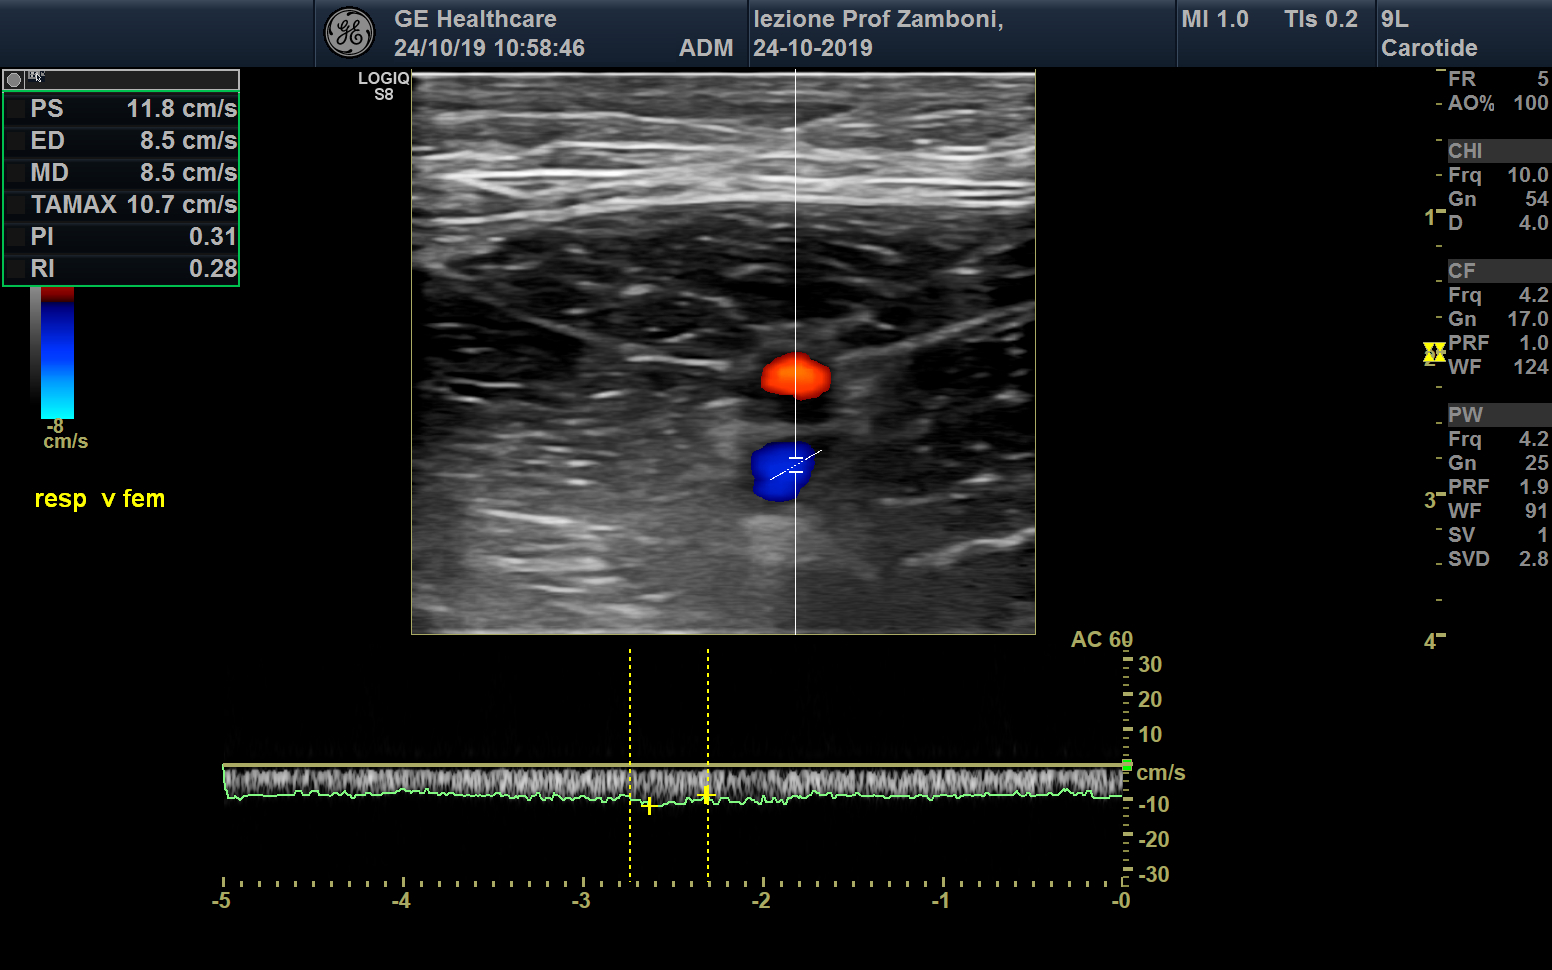

PW V. Femorale respiro

JPEG image icon PW V. Femorale respiro.jpg — JPEG image, 579 kB (593144 bytes)